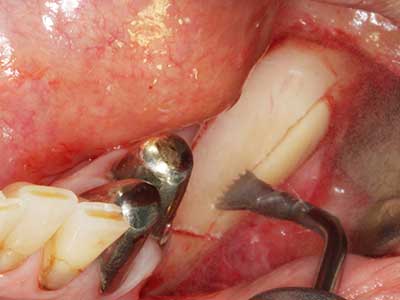

Пиезохирургията има допълнителни предимства при събиране на костни блокове. В допълнение към високата прецизност при остеотомията, описана по-горе, употребата на фините режещи накрайници значително намаляват загубата на материал. Голяма загуба на материал по време на събиране може да се очаква с дебелите накрайници, особено при употреба на борери Линдеман (Lakshmiganthan, Gokulanathan et al. 2012). Базалното разделяне, което е необходимо, особено за присадка на блок при ретромолар, е улеснено от специално създадени правоъгълни триони. В резултат на това, пиезохирургията е разглеждана като прецизна, улеснена и безопасна процедура за събиране на костни блокове в ретромоларното пространство (Happe 2007) (Фиг. 1-12).

Когато се извършват хирургични процедури върху кост в непосредствена близост до чувствителни структури като кръвоносни съдове или нерви, ротиращите инструменти създават значителен риск за ятрогенно нараняване. Пиезоелектрическите апарати могат да бъдат от помощ при препарация на костно покритие и отстраняване на твърда кост близо до нерви, особено за оголване на нервите след ятрогенно нараняване, както и по време на латерализация на нервите за резекционни и реконструктивни процедури или поставяне на имплант (Фиг. 17-20). Лекият контакт между пиезонакрайника и нерва по принцип не води до нараняване, но ако действате непредпазливо с трионообразни движения или приставки за остатъчен костен субстрат, може да причините временно или перманентно увреждане на нерва. Въпреки това, рискът от увреждане се счита за много по-малък, отколкото при употреба на триони или ротиращи инструменти (Pereira, Gealh et al. 2014).